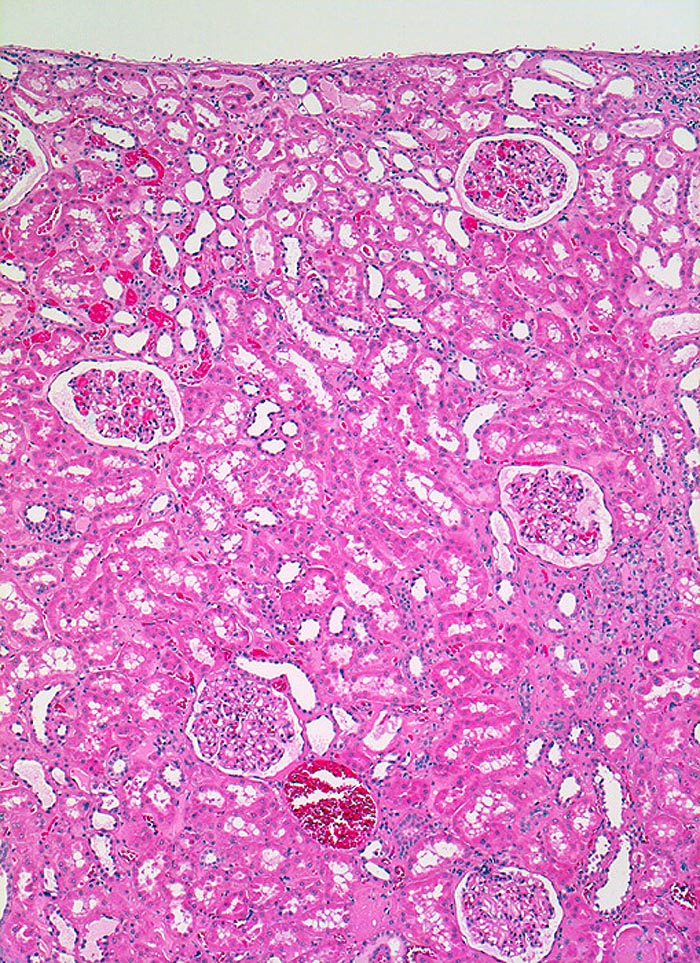

Morphologie:

Im allgemeinen ist die Niere infolge von Glomerulumhypertrophie und Tubulushyperplasie vergrössert und derb, die Oberfläche ist granuliert. Bei schwerer Atherosklerose und fortgeschrittener Niereninsuffizienz kann die Niere auch normal gross oder verkleinert sein. Die Kombination von nodulärer Glomerulosklerose, hyalinen Schlingenkappen (=Proteinthromben in den Glomerulumschlingen (> 1916)) oder Kapseltropfen (> 1907) und Arteriolosklerose in Vas afferens und efferens ist beweisend für eine diabetische Nephropathie. Jede einzelne Läsion für sich genommen ist aber unspezifisch. Eine noduläre Glomerulosklerose kann auch vorkommen bei membranoproliferativer Glomerulonephritis (> 2652), Leichtkettenglomerulopathie oder Amyloidose (> 2019). Der nodulären Glomerulosklerose geht bei Diabetikern eine diffuse Glomerulosklerose (> 1906) voraus. Dabei zeigen die glomerulären Basalmembranen und das Mesangium eine progrediente gleichförmige Verbreiterung. Bei der nodulären und diffusen Glomerulosklerose handelt es sich aber wahrscheinlich um zwei pathogenetisch unterschiedliche, sich überlagernde Krankheitsbilder. Typisch bei Diabetikern ist im Unterschied zur arteriellen Hypertonie die Arteriolosklerose von Vas afferens und efferens (> 1911) und oft auch der Vasa recta. Intrarenale Arterien können eine Atherosklerose mit Atheromen zeigen. Subendotheliale Proteinablagerungen teilweise mit Verschluss der Glomerulumschlingen (Schlingenkappen) und knotige Proteinablagerungen in der Bowman'schen Kapselbasalmebran (Kapseltropfen) gehören zu den sogenannten exsudativen Läsionen (> 1919) (> 1920) der diabetischen Nephropathie und führen zu Synechien sowie zur globalen Glomerulosklerose. Gleichzeitig mit den Glomerulumveränderungen treten tubuläre Basalmembranverbreiterungen auf, später eine Tubulusatrophie und interstitielle Fibrose mit Begleitentzündung. Auch die Basalmembranen der peritubulären Kapillaren sind verdickt.

Morphologische Merkmale:

• Verbreiterung des Mesangiums mit Ausbildung von Knoten(noduläre Glomerulosklerose).

• Exsudative Läsionen: Hyaline Schlingenkappen (Proteinthromben in Glomerulumschlingen, im virtuellen Präparat nicht sichtbar) und Kapseltropfen (Proteinablagerungen im Bowman’schen Kapselraum).

• Arteriolosklerose von Vas afferens und efferens (Gefässwandhyalinose durch Ablagerung von Plasmaproteinen und Lipiden in der Gefässwand).